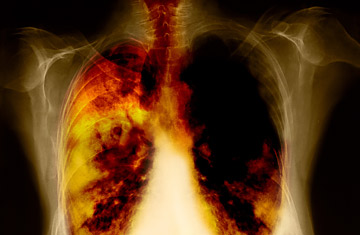

关于肺癌

肺癌发生时,肺部内的正常、健康的细胞被破坏和变异。正常情况下,免疫系统可以控制细胞的损坏和突变,但是,若是免疫系统无法跟上细胞变异的速度,癌症形成。香烟烟雾中有几种化学品,认为可让肺细胞受损,并招致癌症。